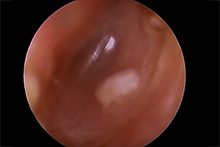

耳内視鏡(ビデオオトスコープ)で見た耳の状況

きれいになった状態の耳

犬の耳 1

犬の耳 1 犬の耳 2